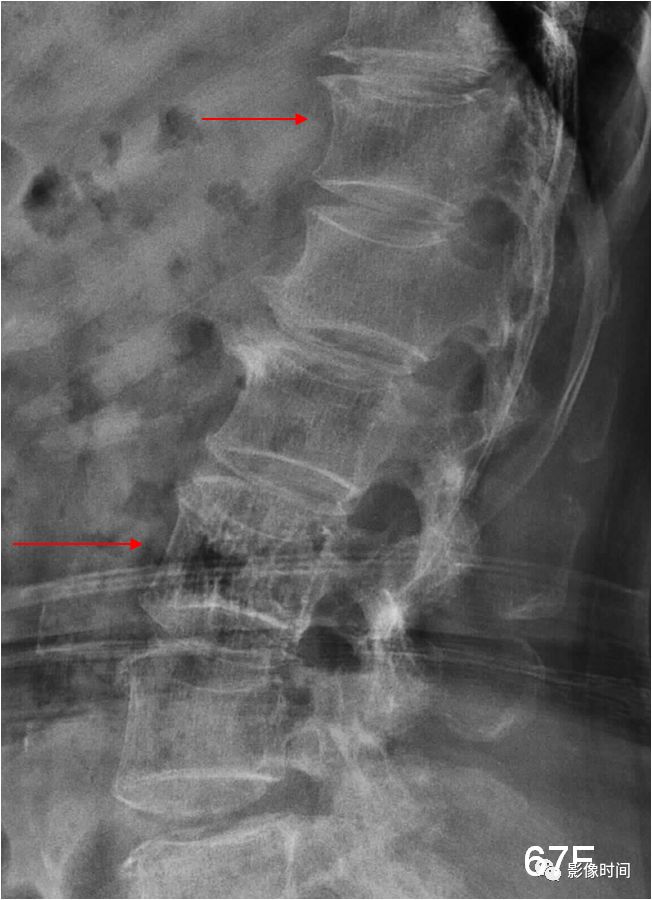

27子弹形椎

子弹形椎(Bullet-shaped vertebra)

子弹形椎指的是椎体的一种形态,即椎体前部呈楔形变尖,类似子弹样。

此名称一般用于描述软骨发育不全的椎体形态改变,但也可以见于黏多糖病和先天性甲状腺功能减退。

(引用自:https://radiopaedia.org/articles/bullet-shaped-vertebra-3)

典型病例

病例 1,5 月男孩,软骨发育不全。脊柱侧位片课件胸腰段后凸,部分椎体呈子弹形(黑箭)。

病例 2,2 岁男孩,软骨发育不全。腰椎侧位片可见椎体呈子弹形(黑箭),另外还可以见到椎体后缘扇贝样凹陷,正位片课件典型的腰椎弓根间距逐渐缩小(红线)。